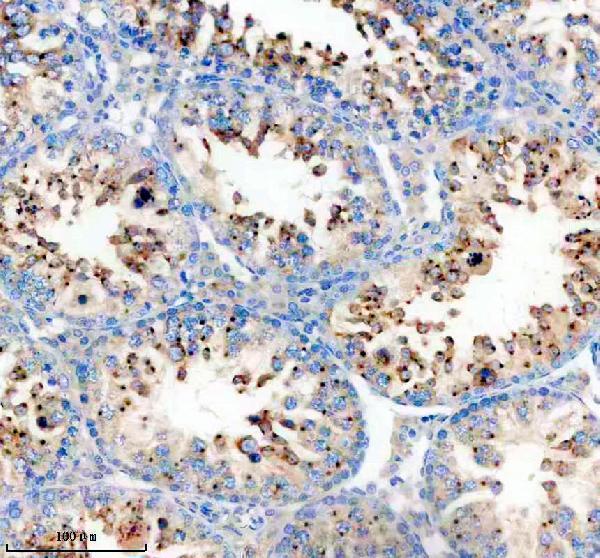

Required for normal acrosome formation during spermiogenesis and normal male fertility, probably by promoting colocalization of JAM2 and JAM3 at contact sites between germ cells and Sertoli cells (By similarity). Mediates ER stress- induced unconventional (ER/Golgi-independent) trafficking of core- glycosylated CFTR to cell membrane (PubMed:21884936, PubMed:27062250, PubMed:28067262).

Golgi apparatus membrane; Lipid-anchor. Endoplasmic reticulum membrane. Golgi apparatus. Detected in the intermediate Golgi, membrane-associated (By similarity). ER stress triggers its relocalization from Golgi to ER membrane (PubMed:27062250, PubMed:28067262).